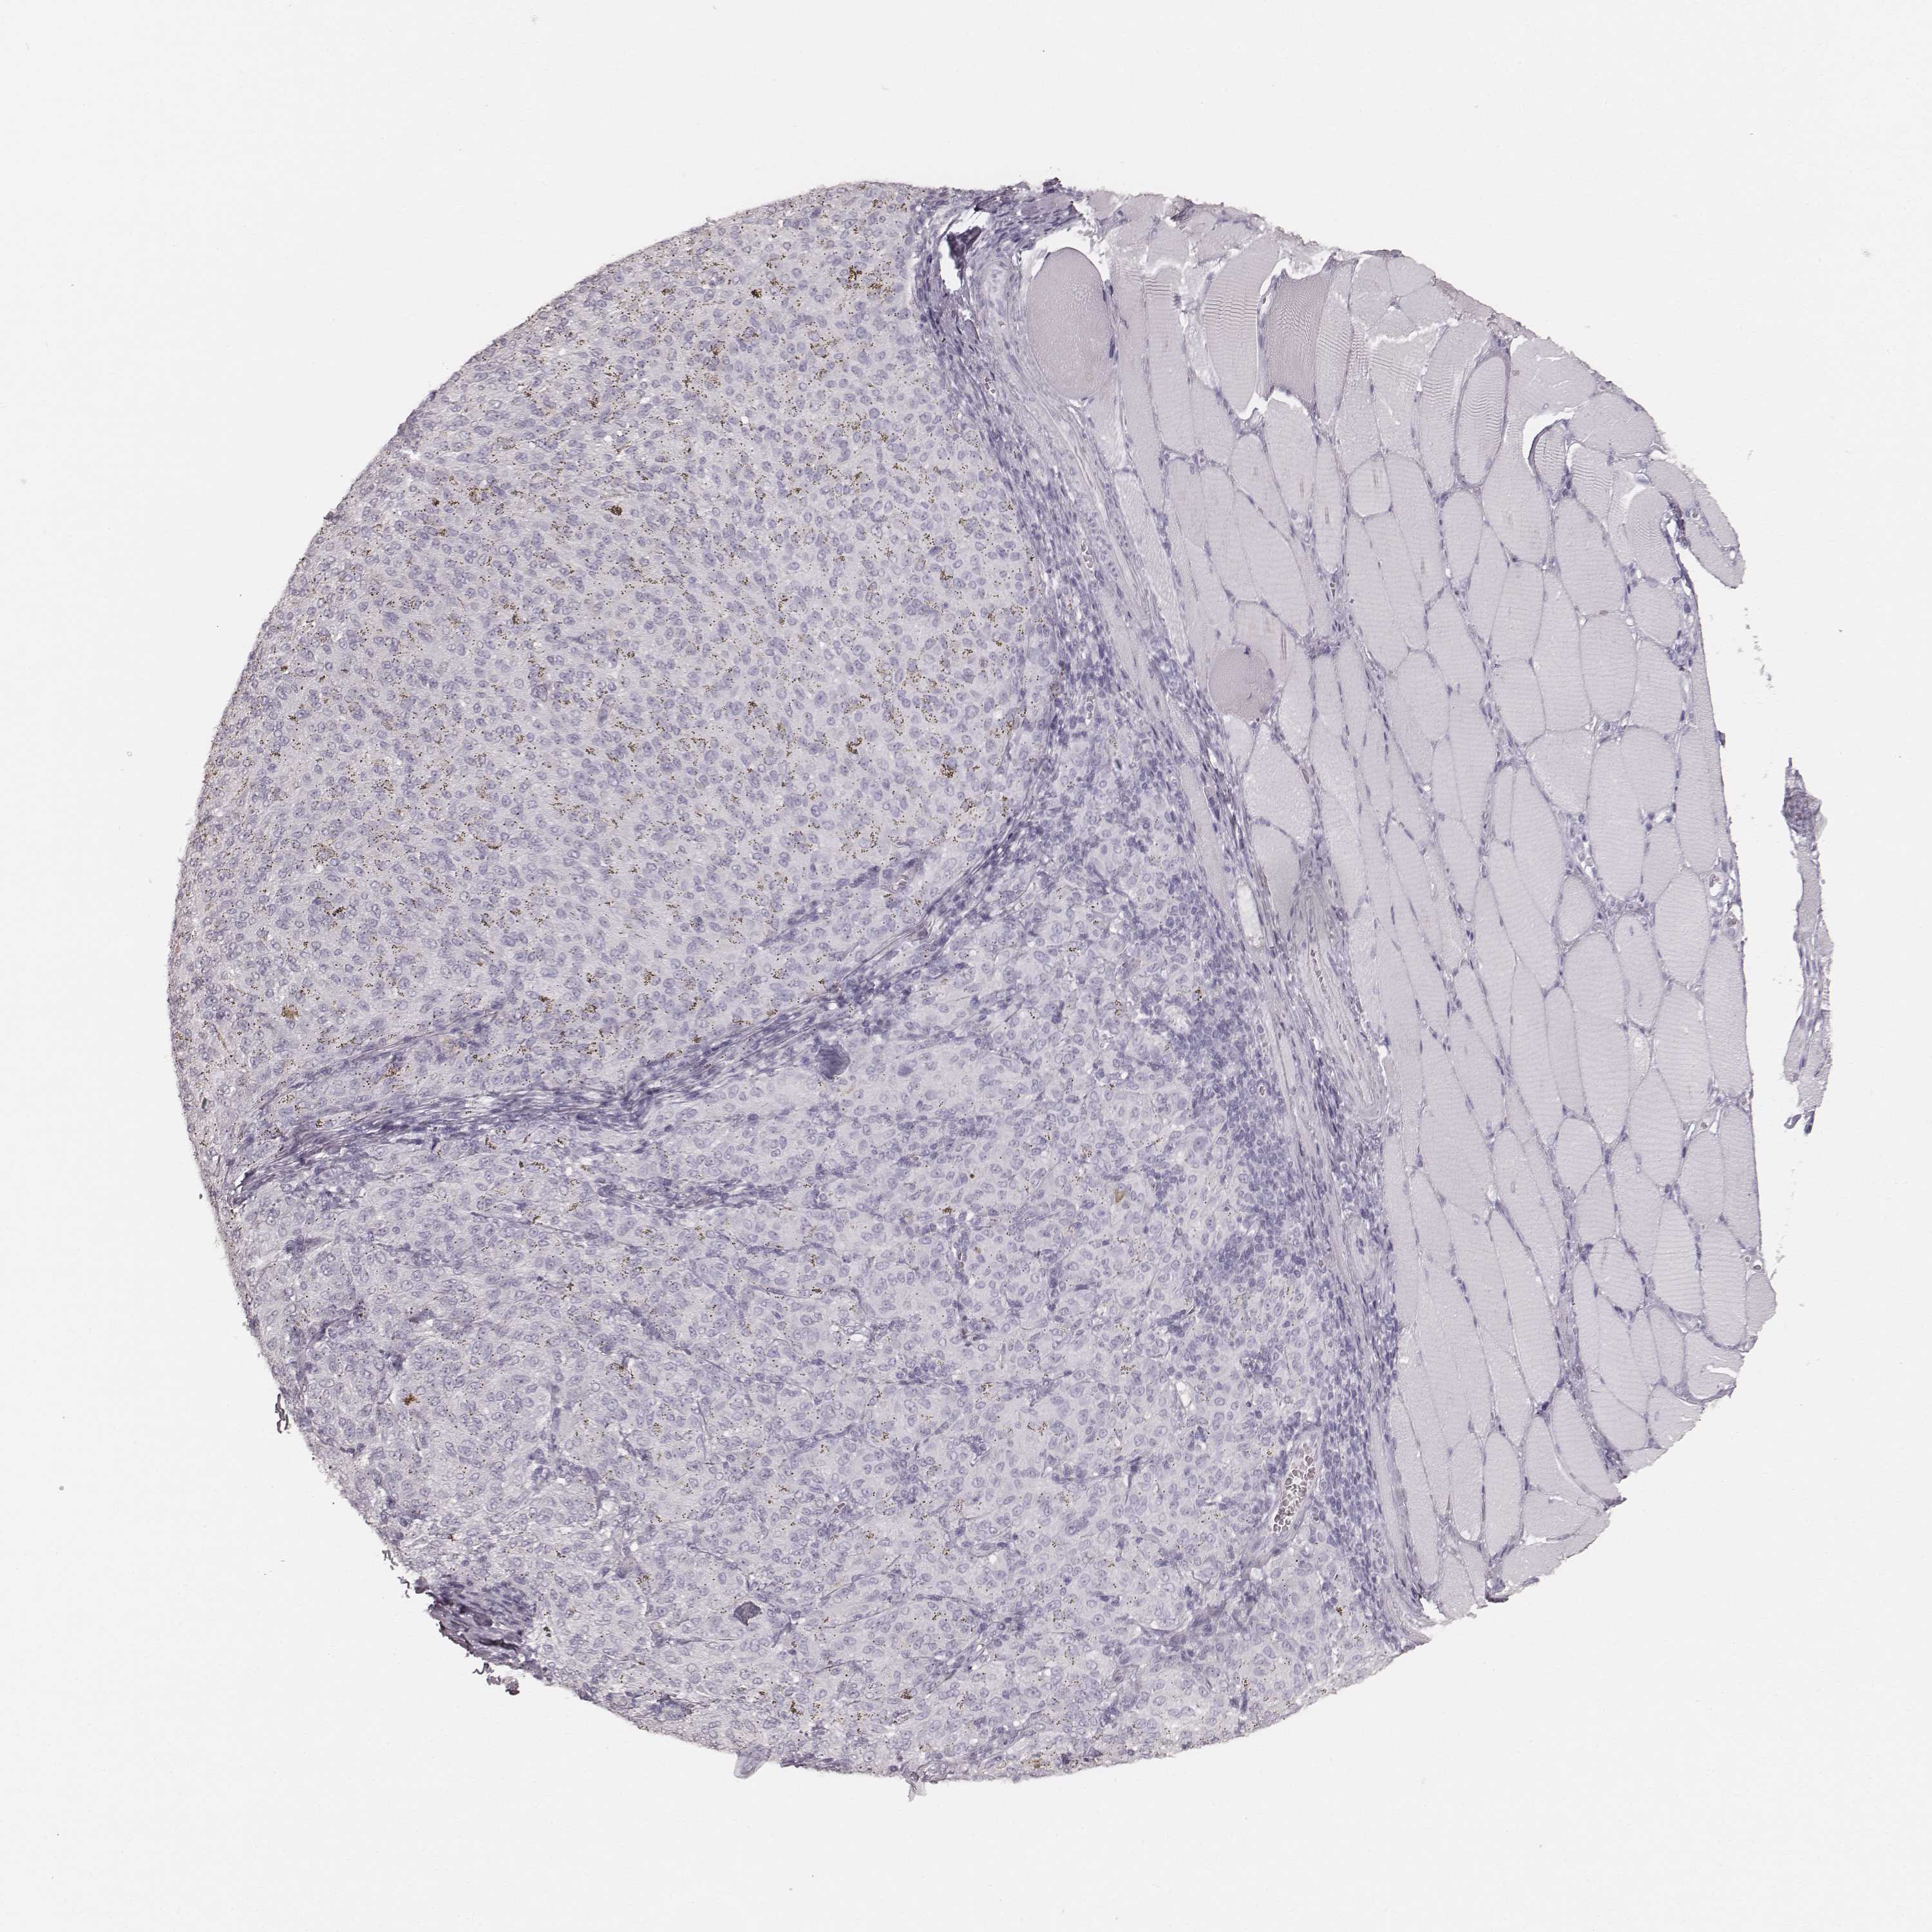

MELANOMA - Protein expressioni

A mouse-over function shows sample information and annotation data. Click on an image to view it in a full screen mode. Samples can be filtered based on level of antibody staining by selecting one or several of the following categories: high, medium, low and not detected. The assay and annotation is described here.

Note that samples used for immunohistochemistry by the Human Protein Atlas do not correspond to samples in the TCGA dataset.

Antibody stainingi

Antibody staining in the annotated cell types in the current human tissue is reported as not detected, low, medium, or high, based on conventional immunohistochemistry profiling in selected tissues. This score is based on the combination of the staining intensity and fraction of stained cells.

Each image is clickable and will lead to virtual microscopy that enables deeper exploration of all samples and also displays staining intensity scores, fraction scores and subcellular localization as well as patient and tissue information for each sample.

Antibody HPA055194

Antibody HPA072208

Staining

High

Medium

Low

Not detected

Intensity

Strong

Moderate

Weak

Negative

Quantity

>75%

75%-25%

<25%

None

Location

Nuclear

Cytoplasmic/membranous

Cytoplasmic/membranous,nuclear

Malignant melanoma, NOS

Malignant melanoma, Metastatic site